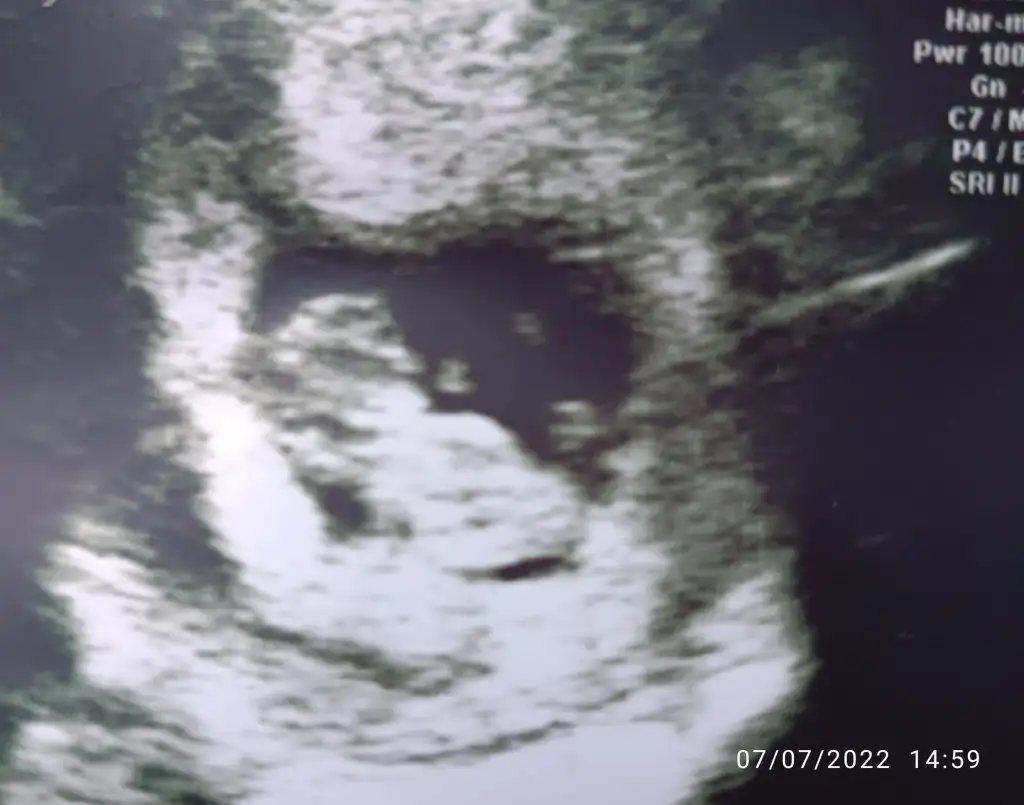

İyi haberler, kalp atışı iyi, buyuklugu tam haftasiyla uyumluymus.10 hafta 3.12 cm.5 gündür aktif kanamanın olmamasi iyi dedi.

Bir de ilk defa hareket ettigini gördüm iki eliyle yüzünü ovusturuyordu

Kötü haber kanama alanlarım artmis .ustte vardı altta da olusmus . İlk resimde siyah alan da görünen kanama alani beni biraz korkuttu dedi doktor. Plasentaya zarar verebilir plasenta ayrilirsa siddetli kanaman olur zaten dedi.doktora 12. Haftaya gelip rahatlasam artik dedi. Hayir yolumuz uzun 20. Haftalara kadar rahim sekli bozuklugundan kaynaklanan risk devam edecek dedi.